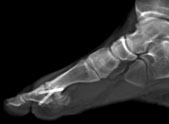

CT des Bewegungsapparates und des Skelettes (Orthopädie)

• Knochen

• Gelenke

Besonders hilfreich ist Computertomographie bei Knochenbrüchen. Daneben wird die CT auch in der Therapie verwendet, z.B. bei der CT-gesteuerten Schmerztherapie und bei CT-navigierten Implantationen und minimalinvasiven Operationen.

Film: Fußskelett mit Schraube

(Zum Abspielen bitte anklicken)